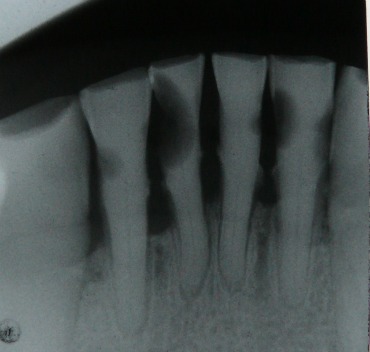

It can be difficult to see a cavity at this stage because the enamel is normally still intact, even though the tooth has been partly hollowed out inside by decay. Your dentist will be able to check your teeth with X-rays. This will reveal any cavities or decay.

An X-ray of lower front teeth with black  areas indicating tooth decayX-ray of tooth decay